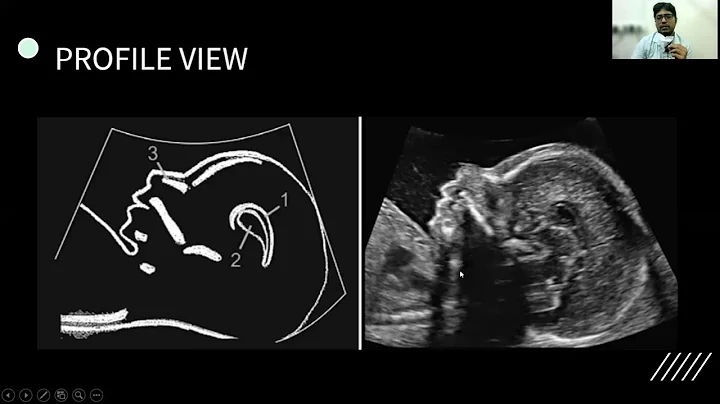

Anomaly Scan (18-22 Weeks) | Dr. Siddhartha Sharma | Consultant Radiologist At Dg Diagnostics

Welcome to the official DG Diagnostics YouTube channel! I'm Dr. Siddhartha Sharma, a Consultant Radiologist, and in this video, ...